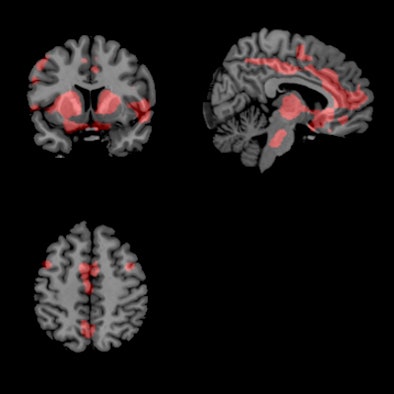

Functional MR images for patients who took the placebo pill and were off the L-DOPA medication indicated a large increase in oscillatory activity in the basal ganglia that spread to other regions of the brain like a ripple effect. When patients were given L-DOPA, their oscillatory brain activity was suppressed, and the brain essentially quieted down.

| Functional MR images of patients who were given placebo pills and were off medication show areas of increased connectivity (red); fMR images of patients who received L-DOPA to suppress brain activity show fewer areas of connectivity (blue). Images courtesy of Rachael Seidler, PhD. |